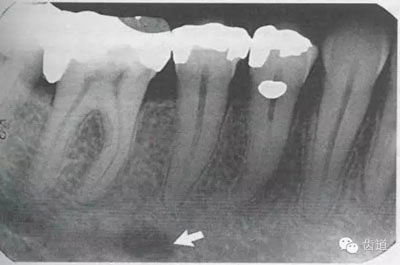

4)外斜線:

由升支前緣下部斜向前下方,為一密度高的帶狀影像。常重疊在第二、三磨牙牙冠處、頸部或根部,使牙髓室或根管不能清晰顯示

5)下頜管:

位于磨牙牙根尖下方,呈寬約為0.4cm凹面向下邊緣整齊的帶狀密度低的影像,其兩側(cè)有密度高的線條狀影像,為下頜管骨密質(zhì)